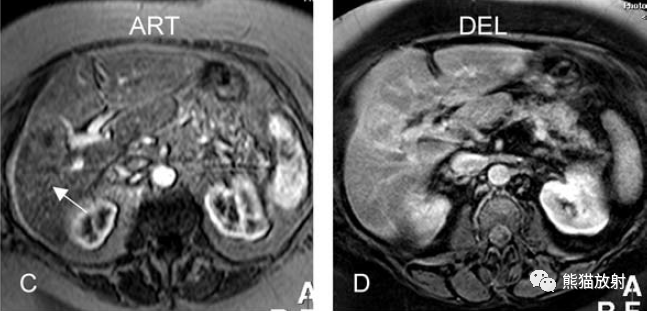

增強(qiáng)動(dòng)脈期(ART):不均質(zhì)強(qiáng)化;

延遲期(DEL):部分廓清,部分持續(xù)強(qiáng)化。

膽囊癌。A~D圖:上方層面,表現(xiàn)如上所述,形成腫物侵及肝臟。E、F圖:下方層面示膽囊壁不規(guī)則增厚,明顯不均質(zhì)強(qiáng)化。